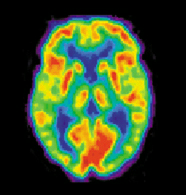

Positron emission tomography

- التصوير الوظيفي، والذي يستخدم لتشخيص الأمراض الأيضية والأضرار واسعة النطاق (مثل مرض ألزهامير) وأيضا في أبحاث علم النفس المعرفي والعصبي وبناء brain-computer interface.

ويمكن للتصوير الوظيفي، على سبيل المثال، معالجة المعلومات عن طريق مراكز في المخ ليتم تصويرها مباشرة. مثل معالجة المنطقة المصابة في المخ والمسئولة عن زيادة الأيضا والتي تظهر مضيئة في المسح. وأحد الاستخدامات المعرفية للتصوير الوظيفي هي استخدامه في التعرف على الأفكار أو قراءة الفكر.